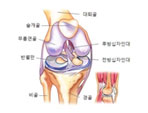

¹«¸

´Ý±â

ÅðÇ༺ °ñ°üÀý¿°

¿¬°ñ¿¬ÈÁõ

¿¬°ñ ¼Õ»ó

ÀÎ´ë ¼Õ»ó